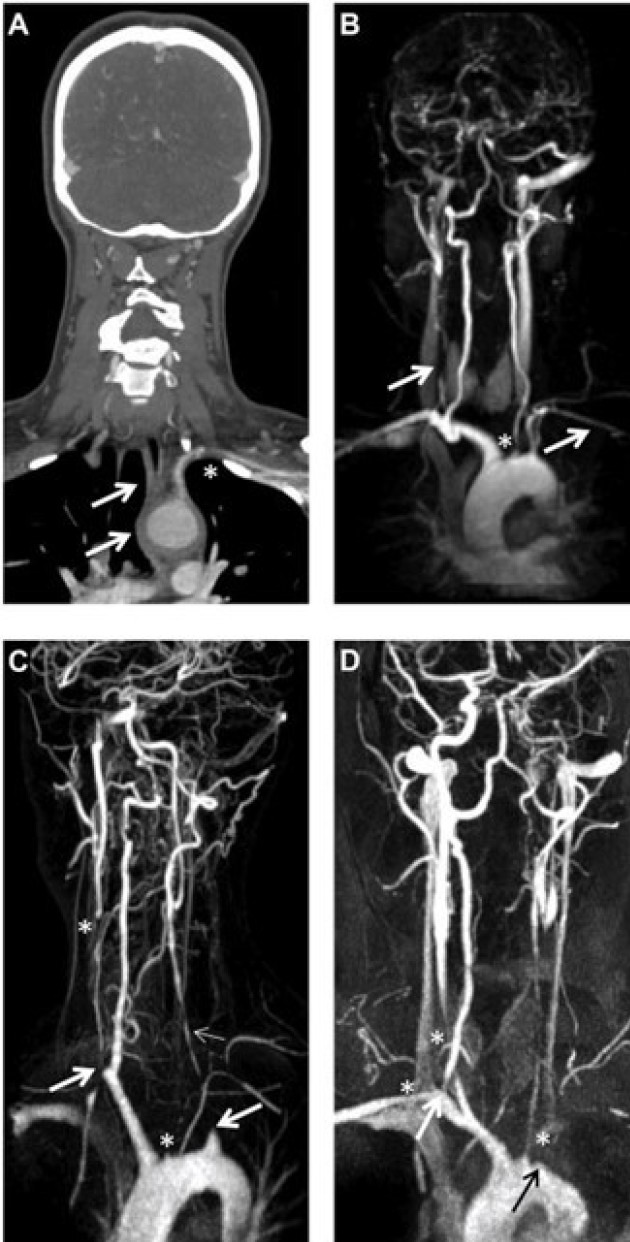

Figure Supra-aortic Takayasu arteritis

(A) CT angiogram of patient 6 demonstrating inflammation affecting the aortic arch that extends to the supra- aortic vessels (brachiocephalic trunk, left CCA and SCA; arrows), with stenosis of the left SCA (star).

(B) MR angiogram of patient 6, with stenosis/occlusion of the right CCA and left SCA (arrows). The star marks the occlusion of the left CCA and proximal narrowing of the left VA.

(C) MR angiogram of patient 3 revealing occluded right and left SCAs (large arrows), occluded CCAs (stars), with an occluded left VA (small arrow) and hypertrophied right VA.

(D) MR angiogram of patient 4 showing occlusion of the left SCA (black arrow), stenosis of the left CCA, right SCA and left VA (stars), with tight proximal stenosis of the right CCA (white arrow). CCA: common carotid artery; MR: magnetic resonance; SCA: subclavian artery; VA: vertebral artery.